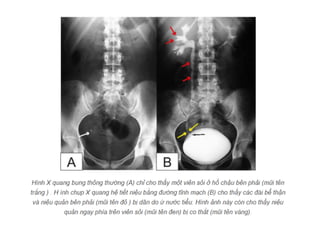

X-QUANG HỆ NIỆU

KUB

• Mục đích:

Đánh giá vôi hóa bất thường của hệ

niệu

Đánh giá tình trạng ổ bụng

Bất thường hệ thống xương

—Kỹ thuật:

Chuẩn bị bệnh nhân:

Tư thế BN : nằm ngửa, phim chụp AP

Yêu cầu: lấy từ cực trên thận đến hết

khớp mu.

• Phân tích kết quả:

- Thận

- Bất thường đậm độ

đường niệu

- Dải mỡ cơ thắt lưng

chậu

- Tình trạng ổ bụng

- Hệ thống xương

• Hạn chế:

- Độ nhạy và độ đặc hiệu phát

hiện sỏi hệ niệu không cao ( ≤

60%) do : sỏi nhỏ, sỏi không cản

quang, trùng lắp vào xương…

- Cần phân biệt với nhiều

nguyên nhân vôi hóa khác trong

ổ bụng ( Vôi hóa TM chậu:

Phlebolith,…)

UIV

Khảo sát

hình thái và

chức năng hệ

niệu.

• Chỉ định:

- Đánh giá tắc nghẽn đường niệu

- Đánh giá bất thường bẩm sinh hệ

niêu- dục

- Đánh giá tổn thương hệ niệu như

tiểu máu, nhiễm trùng, chấn thương, u.

— Chống chỉ định:

- Bắt buộc: mất nước nặng.

- Tương đối: Dị ứng iode, đa u tủy, tiểu

đường, có thai

• Kỹ thuật chụp:

- Chuẩn bị bệnh nhân: thụt tháo

- Chụp phim KUB ngay trước khi chụp UIV.

- Liều thuốc cản quang: 1-2ml/kg cân nặng.

- Phim sớm 01 phút :nhu mô và đường bờ

thận.

- Phim thì 05 phút : đài thận, bể thận.

-Phim thì 15 phút : bể thận, niệu quản.

-Phim thì 30 phút : bàng quang

• Khảo sát hình thái

-Thận: Bất thường số lượng thận, vị trí

và trục thận, bờ thận, kích thước thận.

-Niệu quản

-Bàng quang

• Khảo sát chức năng hệ niệu:

- Đánh giá gián tiếp thông qua sự đào

thải thuốc cản quang theo thời gian.

- Thận câm: đánh giá sau 2-3h.

- Kết luận thận câm thật sự: 24h.